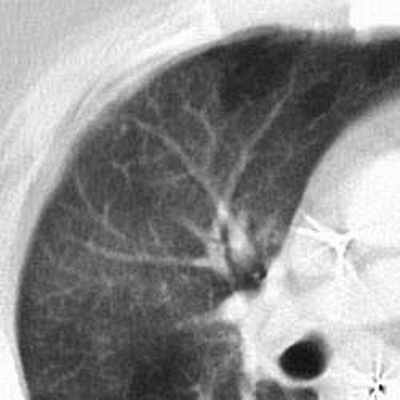

В данном случае пневмония имеет вид, близкий к лучевой картине бронхиолита: в виде сливных очагов в центре лобулярных очагов, обусловленных расширением и заполнением бронхиол. Как правило, при таких формах микоплазменной пневмонии наблюдается выраженный бронхообструктивный синдром, который длительно сохраняется после разрешения этой пневмонии.

Тяжелая форма микоплазменной пневмонии в виде обширных участков по типу «матового стекла» с практически субтотальным поражением легкого.

Рентгенологическая картина этой пневмонии может быть различной.